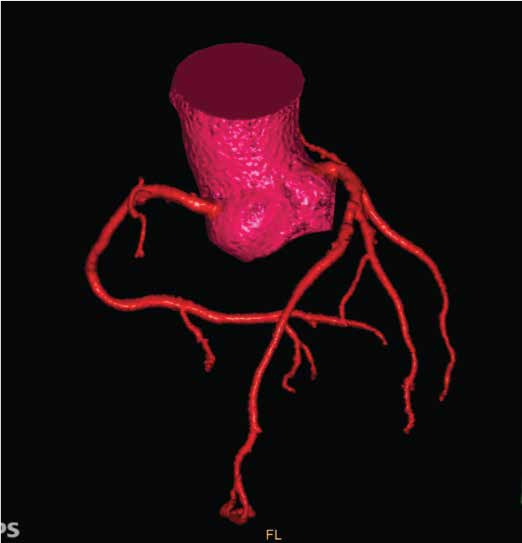

全身各部位血管造影:Incisive CT可以轻松实现大范围CT血管造影(CTA),准确了解血管及相关脏器的形态结构,评估血管及脏器功能,准确判断出血,栓塞、血管瘤、血管畸形、狭窄及肿瘤供血情况,为临床治疗提供极大帮助。

▲ 胸腹部CTA-主动脉夹层一目了然